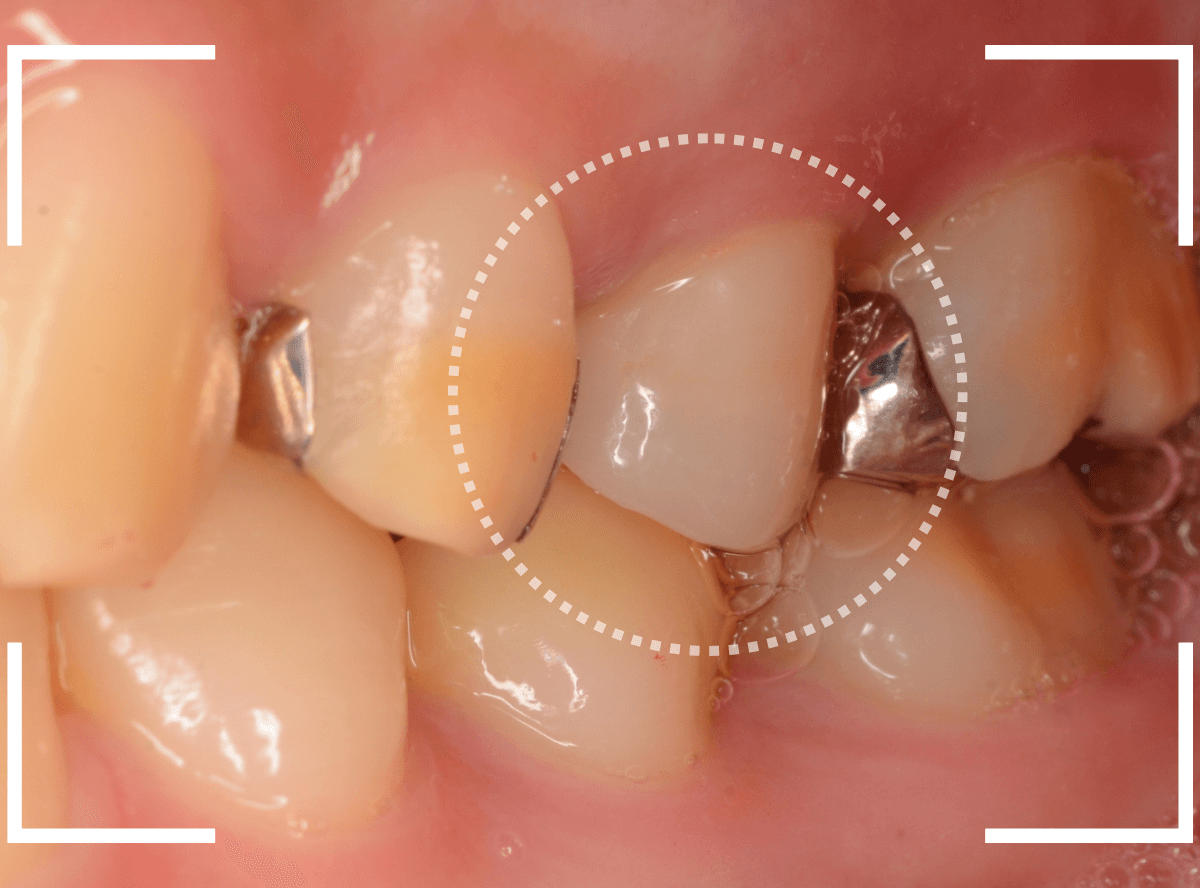

さし歯を入れるスペースがない!

一番奥の歯が土台(コア)の治療までで中断してしまってる患者さんの例です。

本来であれば、この上にさし歯を作らなければいけないのですが、この時点でかみ合ってしまい、さし歯を作ろうにも作りづらい状況でうやむやのうちに治療中断になってしまったようです。

まず、土台の治療をしてから時間が経過していることと、不適合になっている事から、外して中を調べます。

すると、土台の中で虫歯にもなっていました。

(〇部の赤い部分)

こういった事は、レントゲン写真でもよくわからない事が多く、土台を外す治療は本当に神経を使います。

今回は、歯肉の中まで歯が欠損しているので、このまま土台とさし歯を作り直しても、いい結果にはなりません。

患者さんに状況を説明し、歯の周りの歯肉を麻酔をして電気メスでトリミングします。

このように歯の際が歯肉からしっかり出てる状況で製作しないと、さし歯はしっかりお口の中で安定しません。